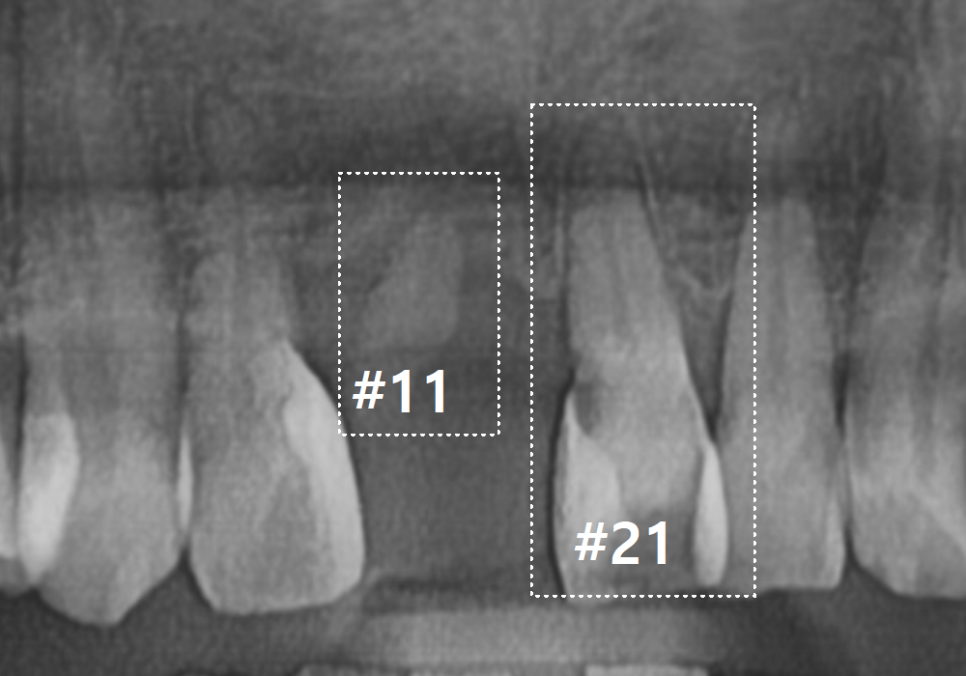

입안을 살펴보니, 오른쪽 앞니(#11)는

이미 부러져서 뿌리만 남은 상태였고,

왼쪽 앞니(#21)는 동요도 3도로

확인될 만큼 심하게 흔들리고 있었습니다.

240523

치과에서 말하는 동요도 3 도는

치아가 앞뒤와 좌우뿐만 아니라,

위아래(수직)로도 쑥쑥 들어갔다

나올 정도로 심하게 흔들리는 상태를 말해요.

뿐만 아니라 충치도 꽤 깊게 진행 중이였어요.

230524

잇몸뼈가 치아를 거의

잡아주지 못하는 단계라

뿌리만 남은 치아와 흔들리는 치아 모두

발치가 불가피했습니다.